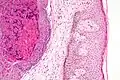

Histologically, molluscum contagiosum is characterized by molluscum bodies (also known as Henderson-Patterson bodies) in the epidermis, above the stratum basale, which consist of cells with abundant large granular eosinophilic cytoplasmic inclusion bodies (accumulated virions) and a small nucleus that has been pushed to the periphery.[19][20]